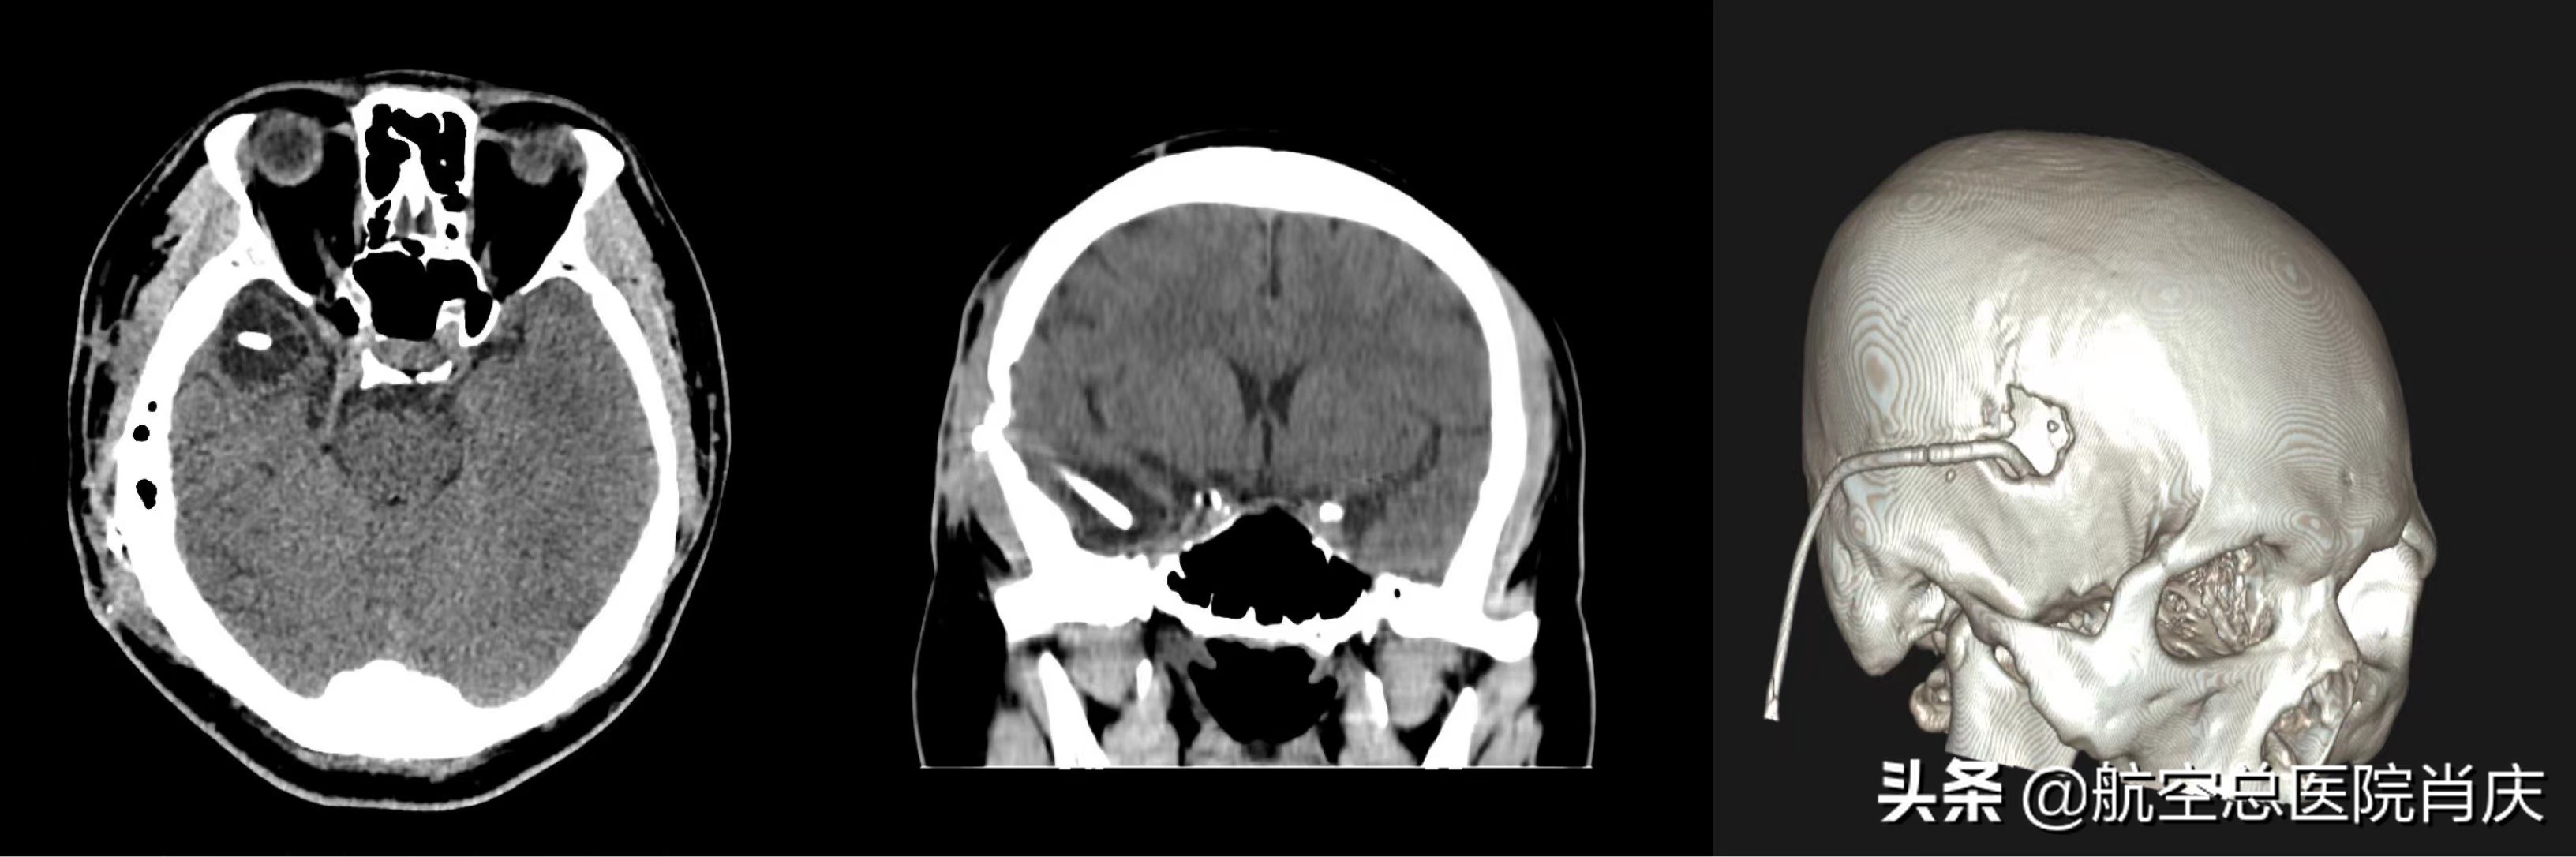

术后

按照治疗方案,先进行间断腰椎穿刺放液缓解症状,腰穿压力均大于330mmH2O,脑脊液化验未见明显异常。随后在局麻下进行分流管调整术,外置原分流管腹腔端,仍间断出现头部胀痛,可疑原颅内段位于蛛网膜下腔内引流所致疼痛。于是在全麻下行分流管调整术,将颅内端分流管调整至脑室囊腔内,并去除原分流阀同时留置长程引流,术后经过对症治疗,患者情况开始好转。鲁先生入院一个月后,肖庆主任团队为其做了脑脊液分流术,术后一周复查头颅及腹部CT示管路位置满意,无明显室旁水肿,患者之前的症状消失,恢复得非常顺利,历时51天的治疗后已经可以出院休养。患者鲁先生和家人非常感谢肖庆主任的专业治疗,一直感慨终于找对了医生!